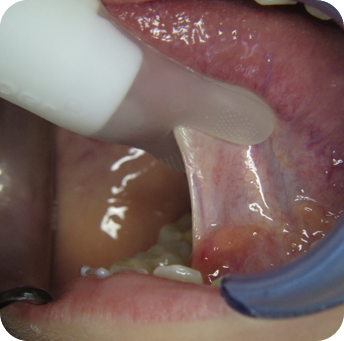

Die chirurgische Durchtrennung kann mit Hilfe einer Schere, eines Skalpells oder eines Laseres durchgeführt werden.

Die Kombination aus der Verwendung eines Skalpells und eines Laseres wird häufig bevorzugt. Die Behandlung kann je nach Patient unter Lokalanästhesie oder einer kurzen Sedierung erfolgen.